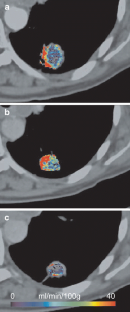

Fig. 5